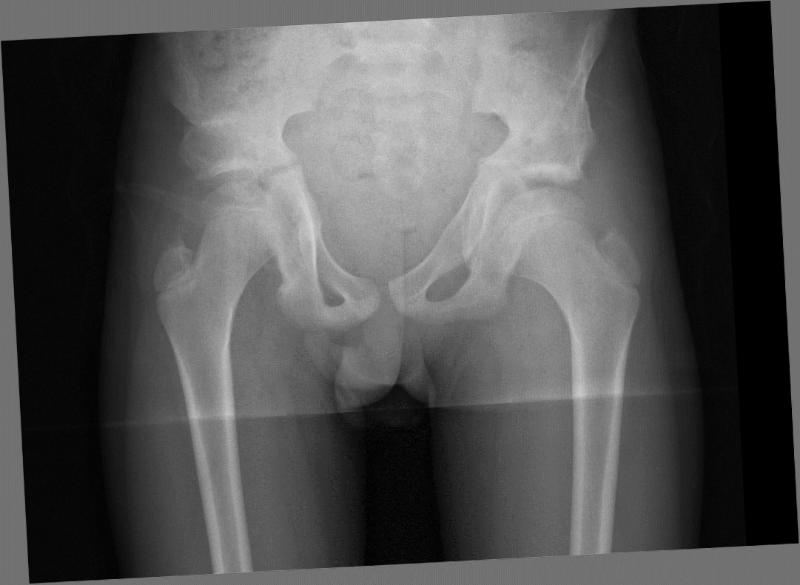

Дисплазия тазобедренного сустава у детей: причины, симптомы и лечение

Узнайте, что такое дисплазия тазобедренного сустава у детей, какие симптомы указывают на патологию, как проводится диагностика и какие методы лечения наиболее эффективны